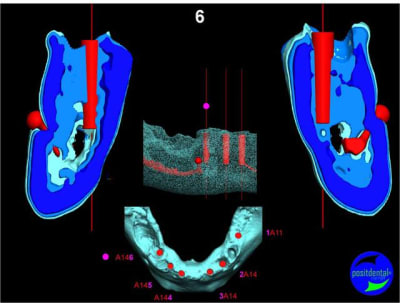

en attendant la pano voici les coupes de la S.I.A.O.

Image33_nwzawb.jpg

Image34_ixvkww.jpg

Image35_orinjf.jpg

Image39_nacsid.jpg

Image40_hkzycw.jpg

Image41_egzryy.jpg

Image42_p57obk.jpg

Image43_jgylho.jpg

Image44_ysqyf8.jpg

Image45_d112br.jpg

Image46_u9eg6l.jpg

Image47_yffnwq.jpg

Image48_ptc9lw.jpg

Image30_exkkml.jpg

Image31_p13zyn.jpg

Image32_ffzd3q.jpg

Image36_jfzwrz.jpg

Image37_inavxh.jpg

Image38_jfa54w.jpg